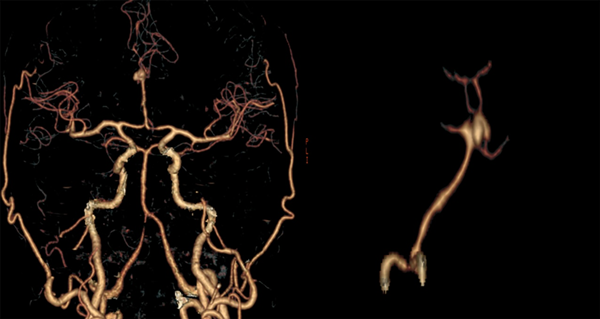

Paciente masculino de 47 años sin antecedentes patológicos de importancia, refiere inicio de enfermedad actual con cefalea súbita, severa, holocraneana, irradiada a región occipitocervical con vómitos en proyectil, desorientación, midriasis e incontinencia urinaria; es remitido a nuestra institución a los 16 días desde el inicio de los síntomas. Al ingreso se observa meningismo, trastornos en el nivel de conciencia e hipertensión arterial. En la tomografía de cerebro (TC) se observa una hemorragia subaracnoidea con un hematoma frontal bilateral. Se realiza angiotomografía cerebral donde se evidencia aneurisma sacular mediano trilobulado de ACAa (Figuras 1 y 2). Al examen físico de ingreso: bradipsíquico, bradilálico, somnoliento, desorientado, GCS 12/15 (respuesta ocular: 3, respuesta verbal: 3, respuesta motora: 6), pupilas isocóricas normorreactivas, sin focalidad de nervios craneales, vías largas: paraparesia 4/5 puntos (Daniels), rigidez de nuca leve y signo de Kernig. Se indica nimodipina 60 mg vía oral, medidas antiedema cerebral. Durante los días 2 y 24 de hospitalización se mantiene con clínica WFNS I, excepto el día 11 de hospitalización, donde se presenta deterioro neurológico por desorientación a WFNS II con evidencia de hiponatremia moderada (129 mEq/L). Se solicita tomografía cerebral simple control en la que se descarta resangrado e hidrocefalia, se indica corrección de sodio plasmático con mejoría evidente del estado neurológico a WFNS I. Se plantea intervención quirúrgica a las tres semanas del ingreso.

Figura 2. Angiotomografía cerebral. En reconstrucción 3D se evidencia circuito anterior: confluencia de ambos segmentos A1 (sin presencia de complejo comunicante anterior) en un tronco arterial único A2, presenta un aneurisma sacular trilobulado mediano en su bifurcación con domos que se disponen hacia arriba y hacia adelante. Cuello: 6.16 mm, alto: 6.39 mm y ancho: 8.17 mm.